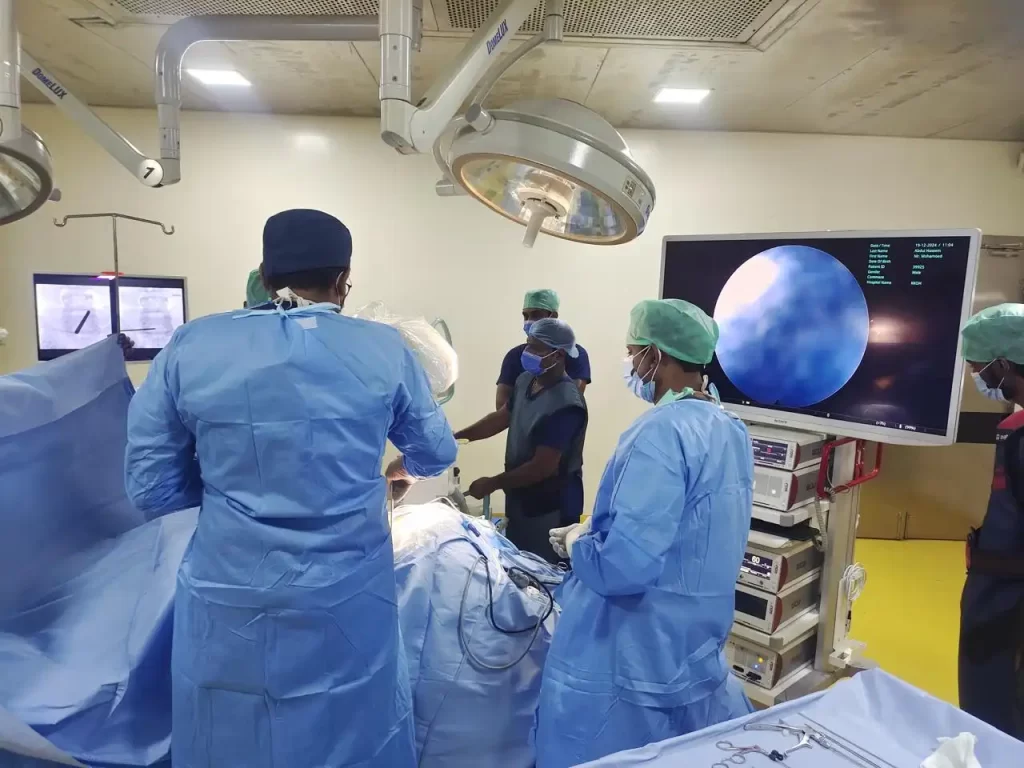

Today, technological advances in optics and the development of advanced camera and display systems such as 4K technology have made spine surgery a simpler and safer procedure. These are known as minimally invasive techniques because they require only small skin incisions. There are two main techniques: microdiscectomy and endoscopic discectomy. In a microdiscectomy, a small incision is made in the skin, and the surgery is performed with the help of an operating microscope that provides a magnified view of the affected area. An endoscope is a thin, specialized telescope that can be inserted into tissues through a small incision to reach the target area. A camera system and display monitor are connected to the scope to view the interior of the body, allowing the surgeon to operate while viewing an enlarged image of the deeper tissues.

Special instruments and equipment are required for this surgery. Using this technique, surgeons can not only remove the disc but also widen the spinal canal in cases of stenosis and relieve nerve root compression caused by other factors, all with the help of the endoscope. This procedure requires specialized training in the use of endoscopic equipment. KKOH has pioneered the use of endoscopic surgery in the treatment of spinal disorders. For further details or to book an appointment with a spine specialist, please contact the reception.

A small instrument called endoscope is introduced through a small stab wound and surgery is performed. Used extensively for disc removal at low back and neck. Dilation of the spinal canal is done with endoscope using specially designed burrs. The major advantages of this procedure are no damage to normal tissues unlike open surgery. Therefore, recovery is early very short hospital stay, minimal pain, the need for pain medications is limited early return to work less chances of complications like dural tear and nerve root damage.

Our endoscopy system uses the advanced 4K technology from Rivo spine, Germany. This technology involves high end image capture system giving natural colours to the tissues.